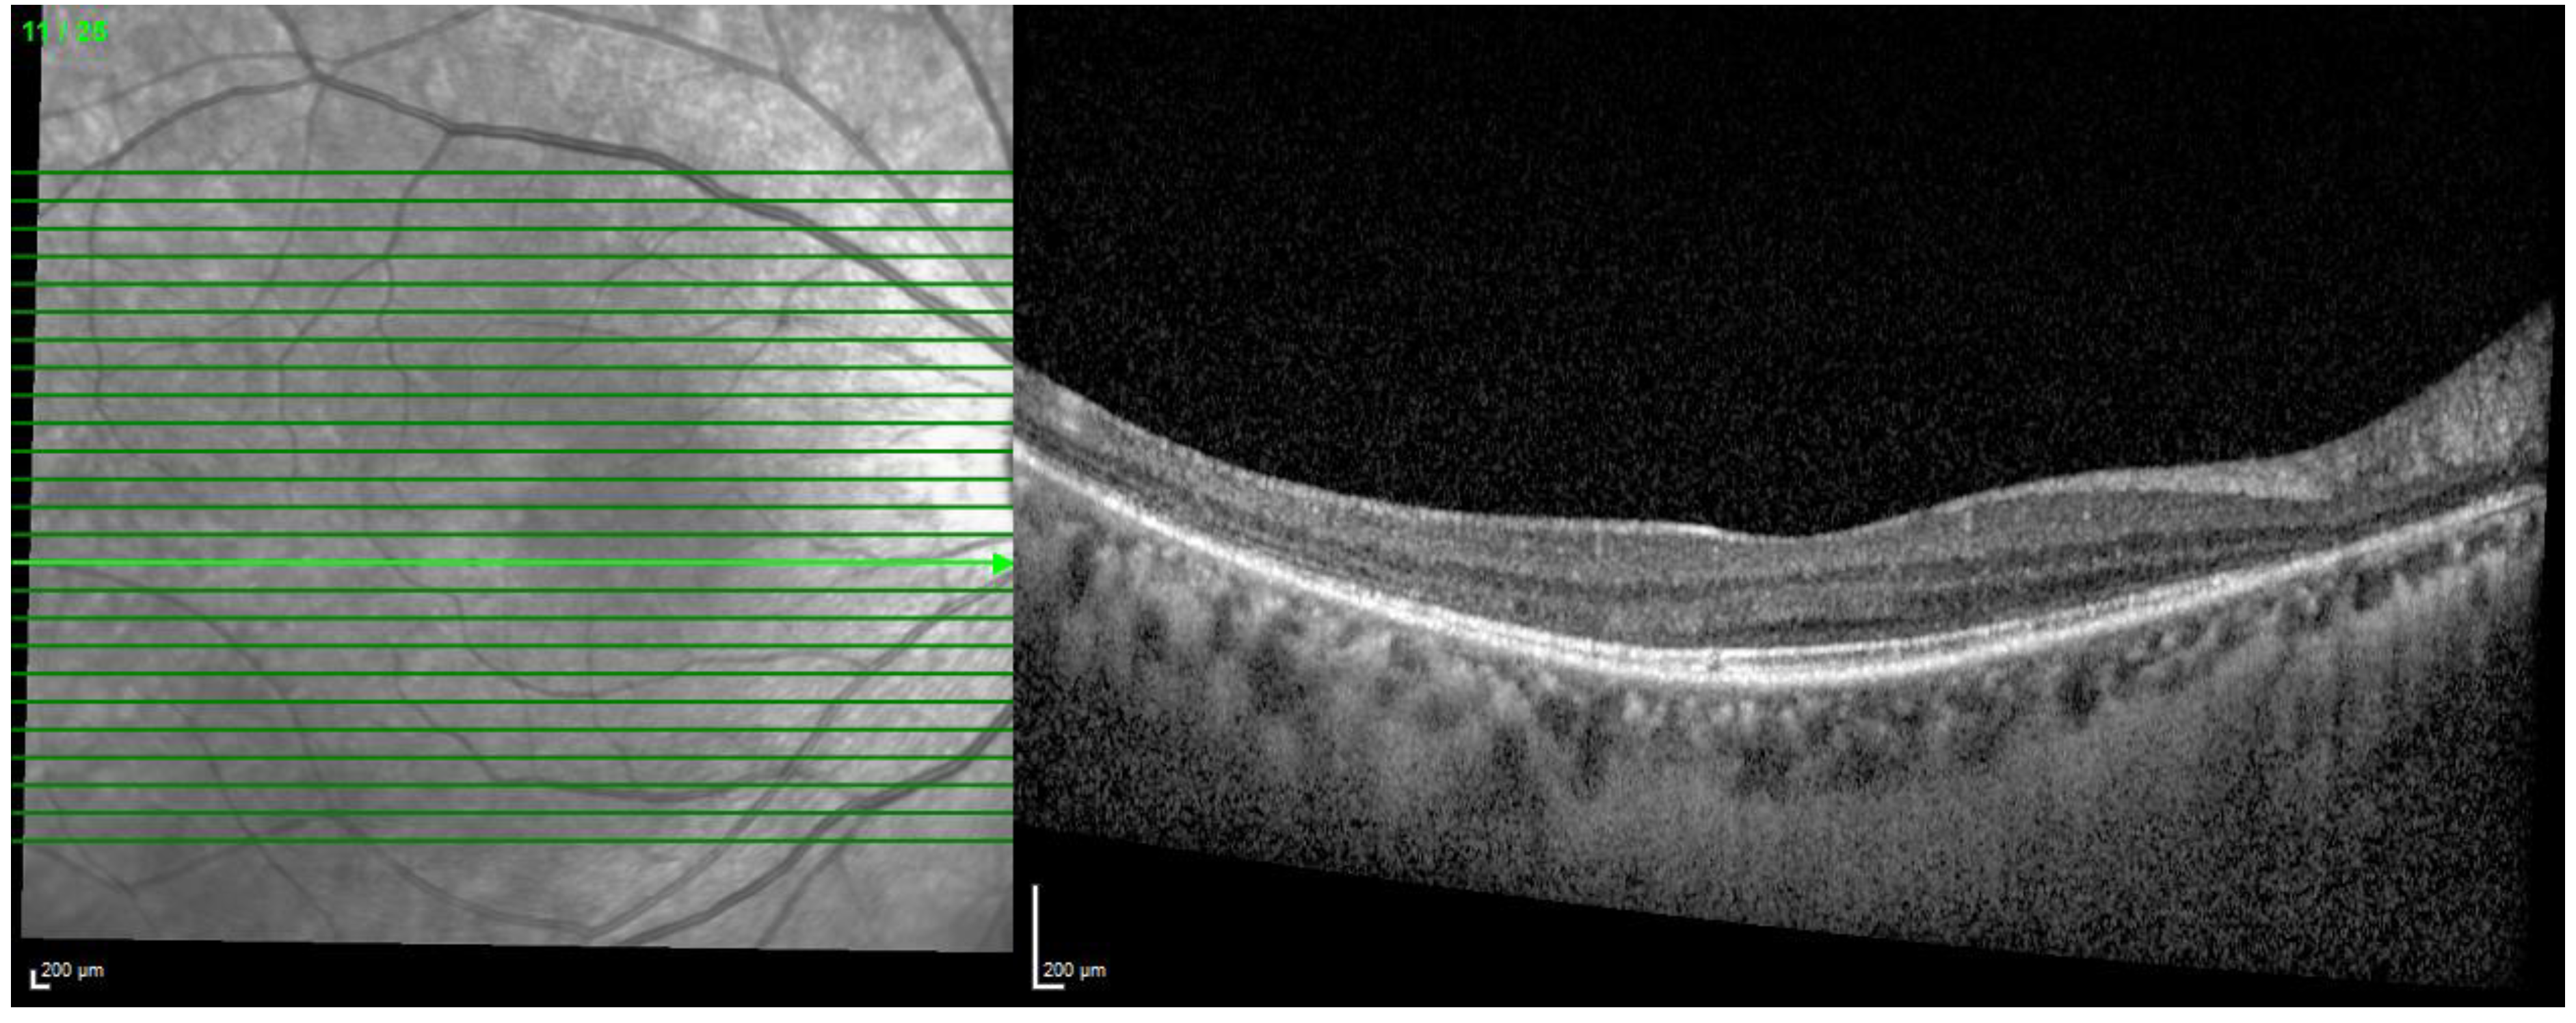

- Ahn, S.J.; Joung, J.; Lee, B.R. En Face Optical Coherence Tomography Imaging of the Photoreceptor Layers in Hydroxychloroquine Retinopathy. Am. J. Ophthalmol. 2019, 199, 71–81. [Google Scholar] [CrossRef]

| En face imaging |

|